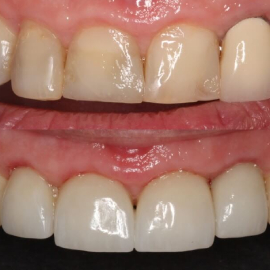

Ceramics can make a smile look nice again

Implant supported teeth

Implant bridge

Single tooth implant